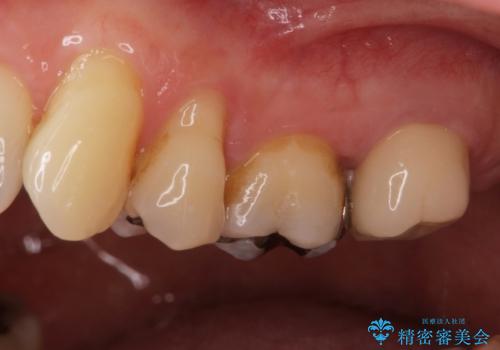

銀歯を白くしたいセラミック治療。

- 奥の銀歯を白くしたいとの事で来院。

痛みはないとの事でしたがレントゲンを撮影したところ根の先に病巣がある事がわかりました。

被せ物、古い材料を徹底的に除去し、ラバーダム防湿にて無菌的処置を行い、セラミックの被せ物で治療を行いました。

病巣は現在縮小しておりまた白い被せ物が入り患者様に満足してもらえました。